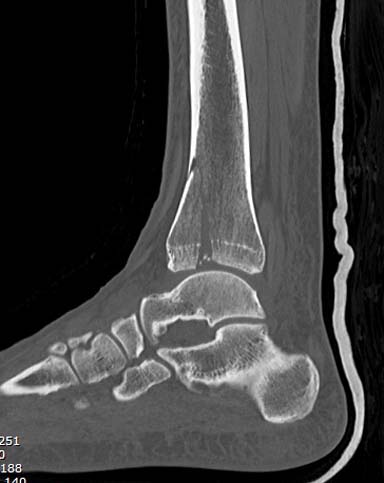

Второй случай в результате скоростной травмы, кроме пилона, вовлечение

других органов! Отек при поступлении и открытый перелом на другой

стороне. В таких случаях нет смысла спешить, и временный наружный

фиксатор на несколько дней. После спадения отека фиксация

передне-наружной пластиной.  Реабилитация - ранние движения, без

нагрузки.